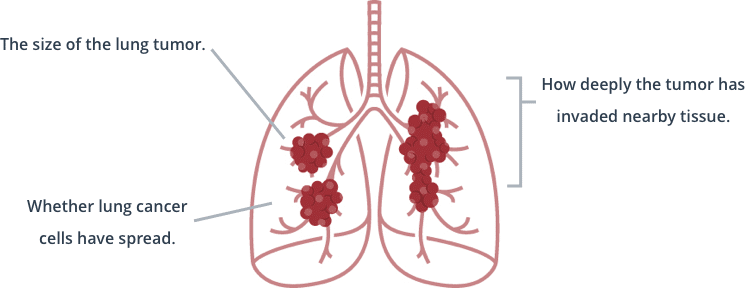

Typically, symptoms of lung cancer do not appear until the disease is already at an advanced stage. The stage or progression of lung cancer is determined by: